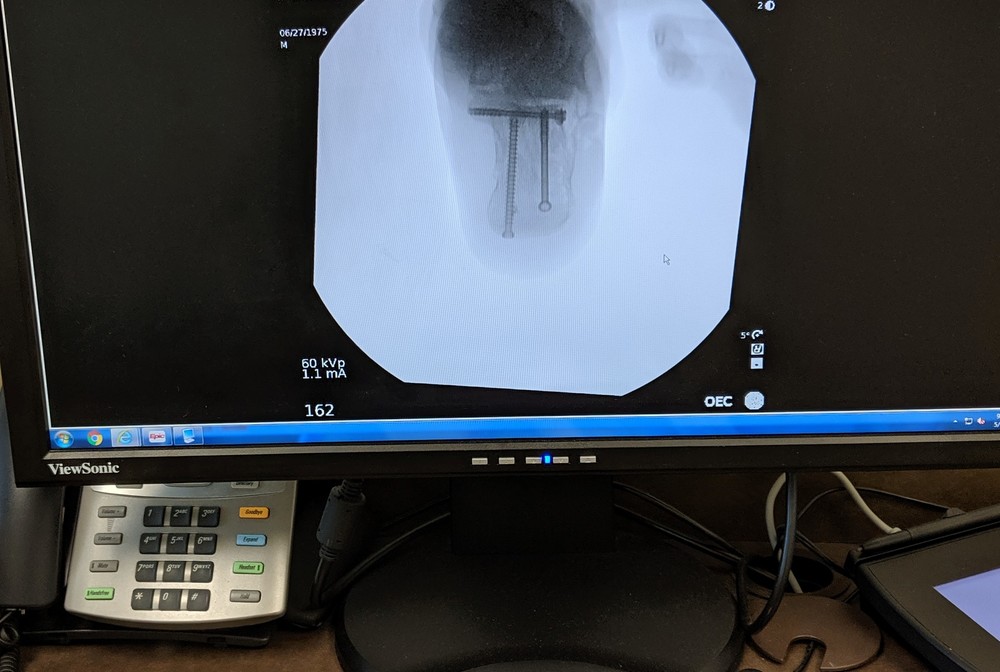

Still in recovery/rehab mode here, went twice to rehab place not much good news,so far, leg needs to come back more up (im minus 15 on it) left to right only little movement , still cant curl toes down, and im 1 week out from hard cast,the people at rehab they good but can only do so much.... now good news ,no pain in it and im putting about 60 to 70 % weight on it...Honestly i think the rehab is the hardest part in this injury, and how lucky you get...Thanks Steve,Jeff ,Bryan and now John for all the nfo Some pics from today, injured led wont come back like other one Some pics from today, (rehab people told me to use compression sock during the day) Before x-ray right when broken ,left after surgery. 2 weeks after surgery. |

these extra entry points are true stab incisions where we put big pins into the bigger chunks of bone to toggle, joystick the fracture back in position. |

I am a surgeon who performs this surgery and a lifer climber. happy to answer questions directly or even review xrays etc...Bottom line with this fracture is the damage to the cartilage and the joint and how well that can be put back together. if the joint isn't broken and alignment can be repaired, then return to active life is possible. Younger, healthier (people) joints fair best. The other challenge comes if there are other injuries/fractures sustained at same time further delaying recovery. Bone takes 6 wks to heal and most people take 6-12 months to total rehab. |